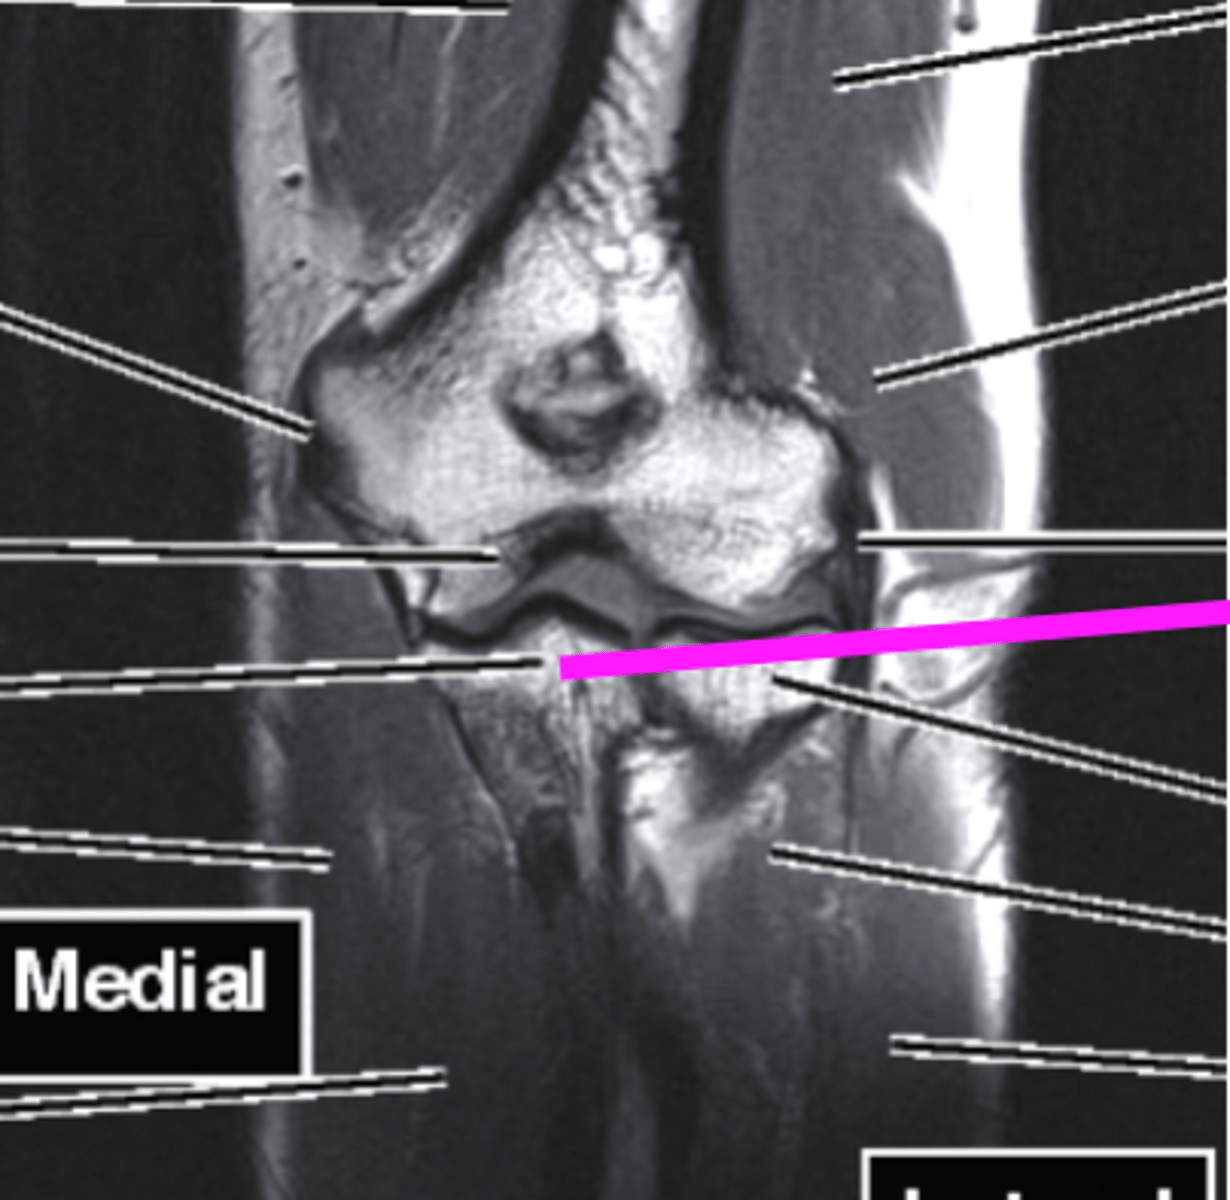

Coronal MRI

what imaging type and view is this?

AC joint

what does the pink line point to?

supraspinatus muscle

superior labrum

inferior labrum